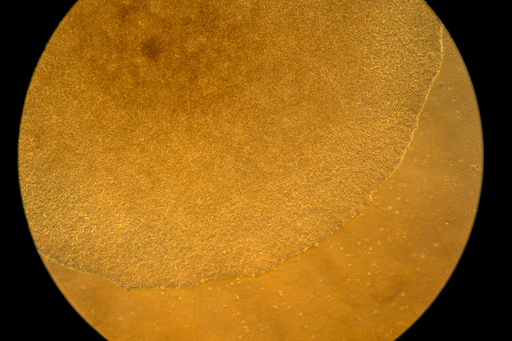

In Green's lab, a computer screen shines with brightly colored dots that resemble a galaxy. It’s a biological map that shows insulin-producing cells in the pancreas of a mouse. Red marks rogue T cells that destroy insulin production. Yellow indicates those peacemaker regulatory T cells — and they're outnumbered.

Green's team aims to use that mRNA to instruct certain immune “generals” to curb the bad T cells and send in more peacemakers. They package the mRNA in biodegradable nanoparticles that can be injected like a drug. When the right immune cells get the messages, the hope is they'd “divide, divide, divide and make a whole army of healthy cells that then help treat the disease," Green said.

The researchers will know it's working if that galaxy-like map shows less red and more yellow. Studies in people are still a few years away.